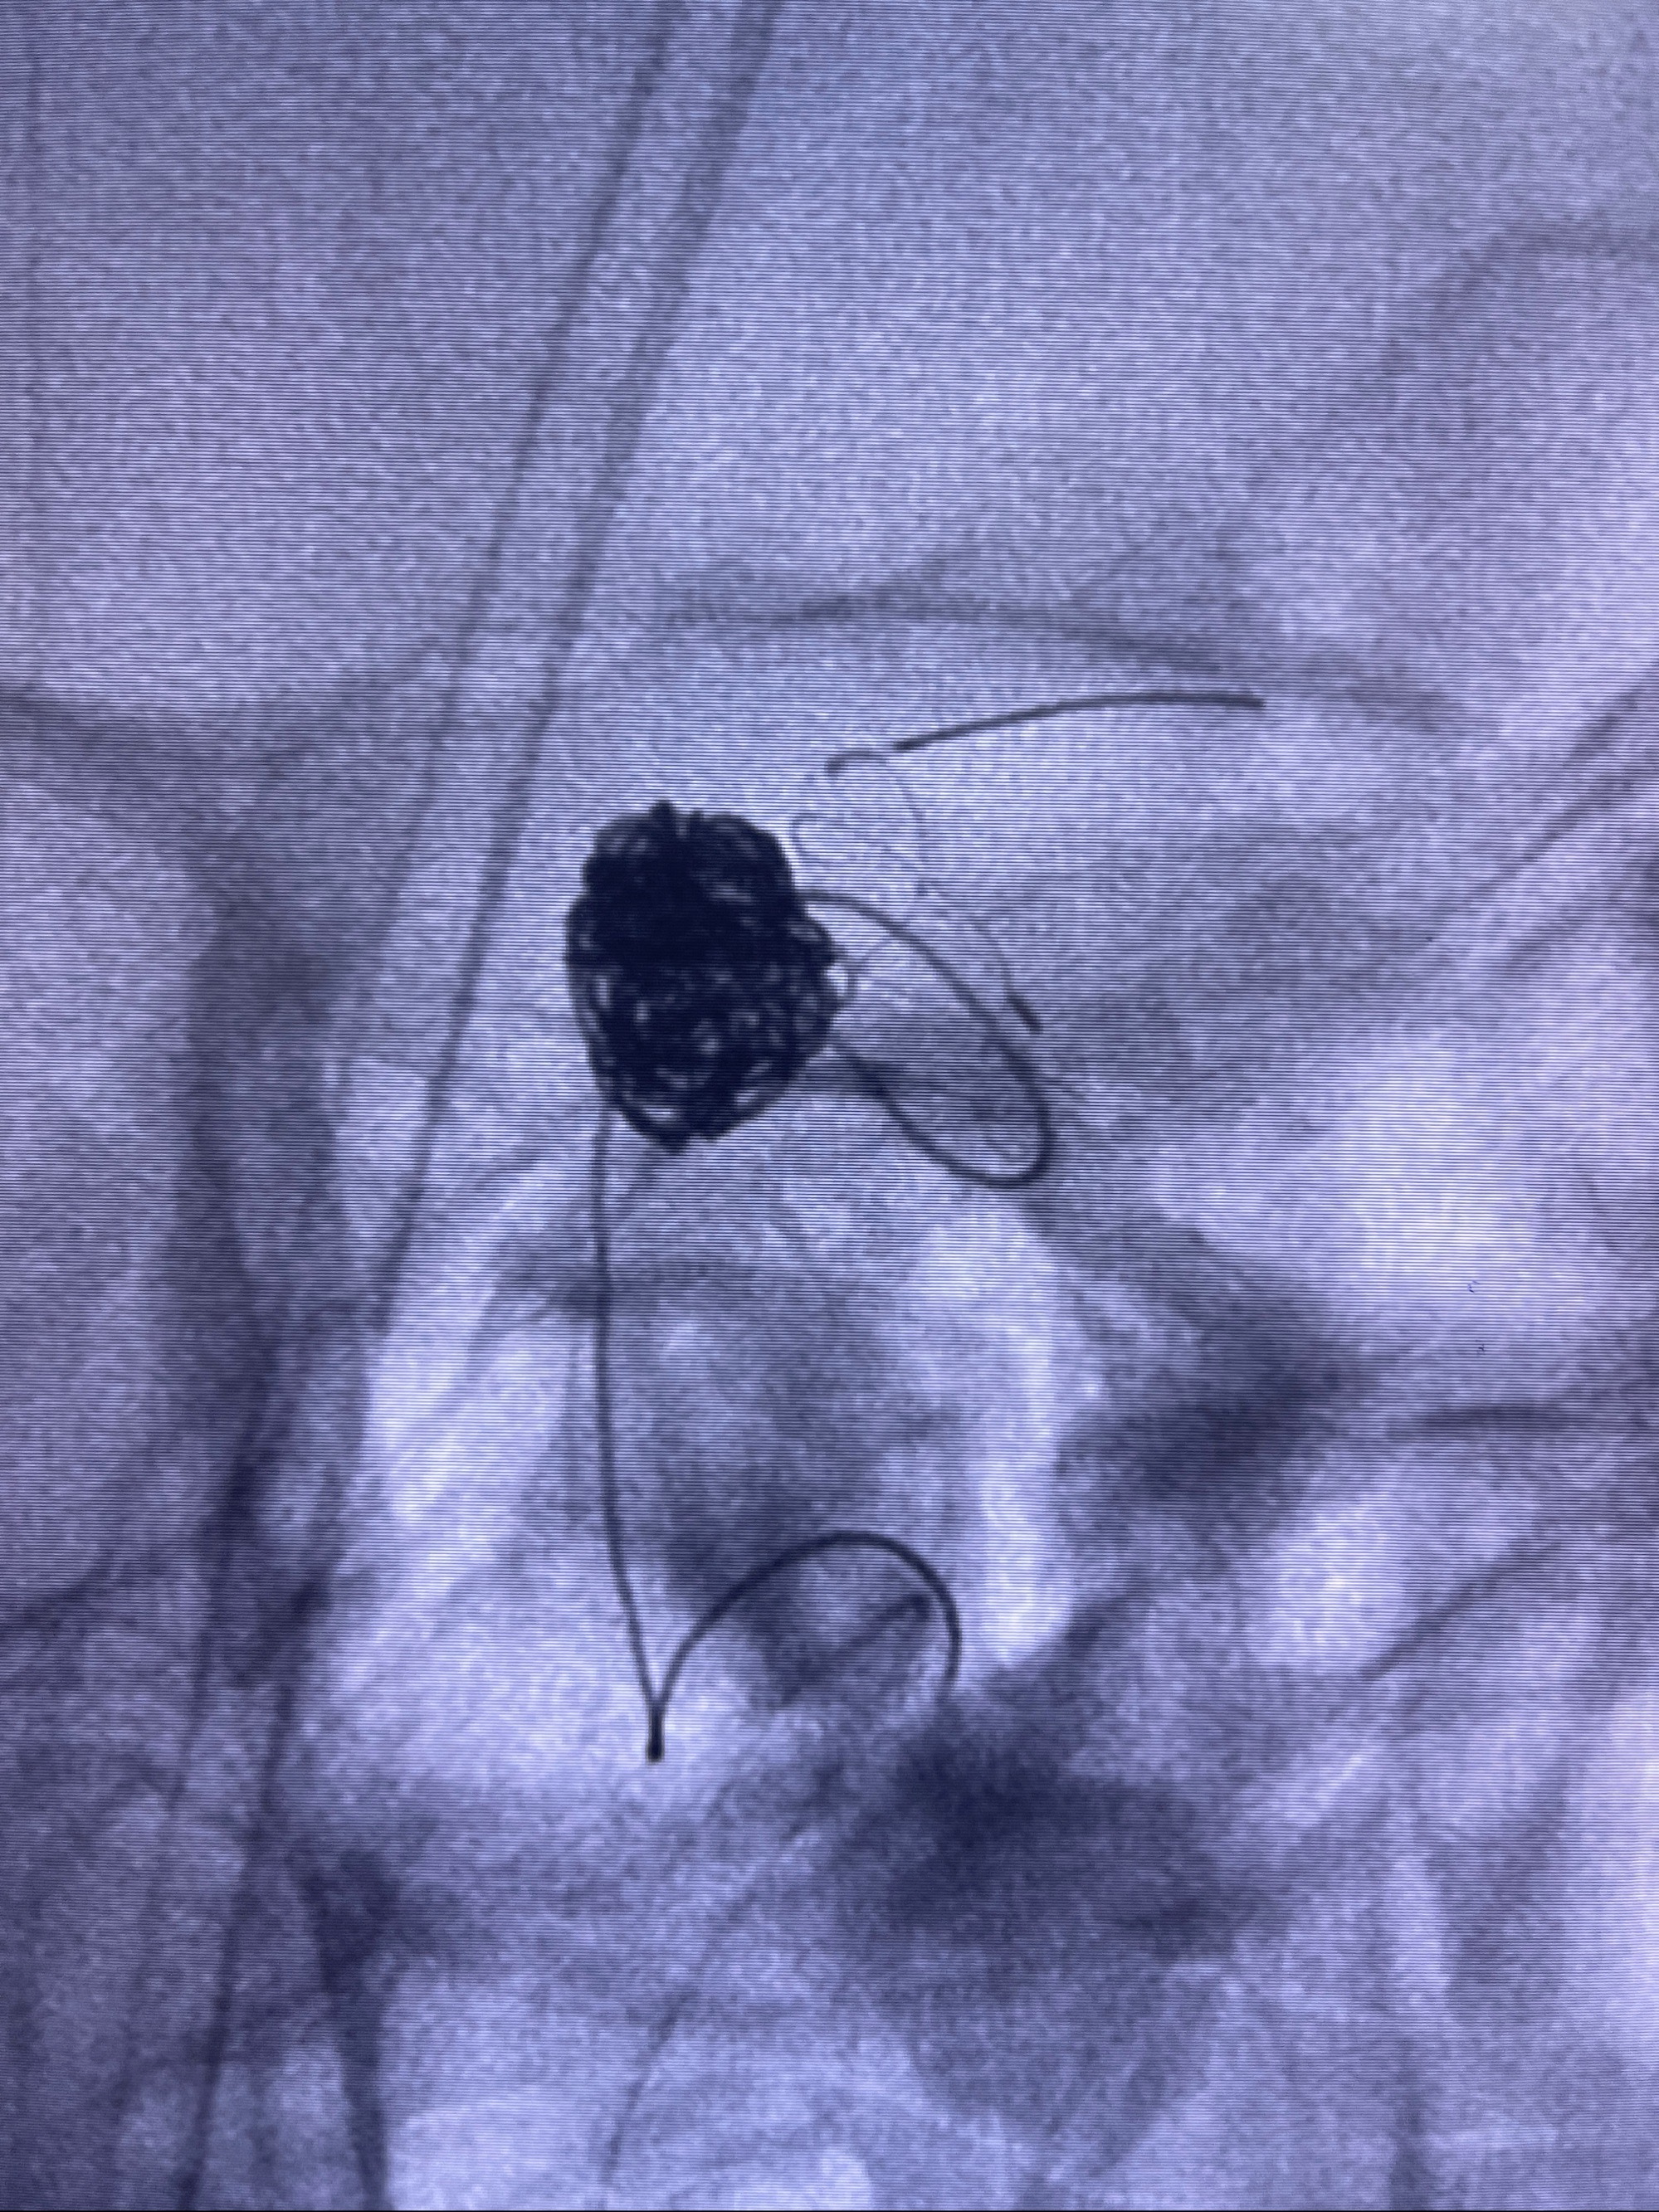

- Tubridge 4.0-20mm密网支架

- 加奇微弹簧圈:7*30/6*20/5*20/2*8

术后3D显示支架贴壁佳